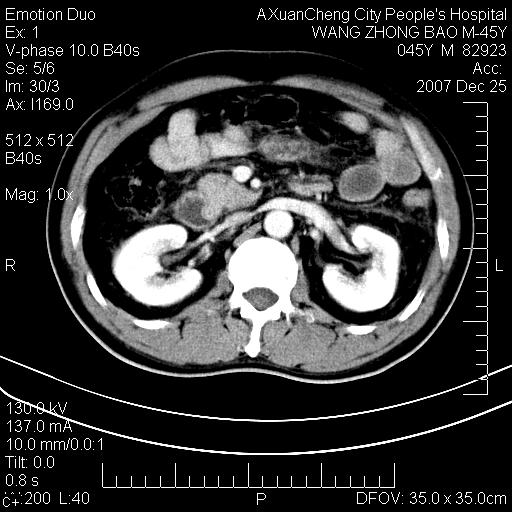

以下是引用卜一在2007-12-25 14:07:00的发言:[br]胰头钩部略增大,与十二指肠壶腹部关系密切,其内明显见软组织密度肿块,明显强化,但肠壁较光滑 柔软。考虑:炎性增生!建议消炎后复查!待除外壶腹部腺癌!

以下是引用zjzjr在2007-12-25 13:35:00的发言:[br]考虑正常的十二指肠乳头部,建议胃镜检查.

以下是引用qiuleiyu在2007-12-25 18:14:00的发言:[br]胰腺增大,周边渗出改变,肾前筋膜明显增厚,示少量积液.胆囊壁毛糙,周边少许渗出,胆总管壁厚,异常强化,然扩张不明显.结合病程急短;考虑;胆管炎,胆囊炎,胆源性胰腺炎可能大,请结合实验室检查及随访.

以下是引用lisihao在2007-12-25 14:23:00的发言:[br]急性水肿型胰腺炎[br]依据:1、胰腺弥漫性肿大,边缘稍毛糙;[br] 2、双侧肾周筋膜增厚,尤以左侧为甚(重要征象)[br] 3、双侧后胸膜增厚(刺激性炎症);[br] 4、结合病史,查血尿淀粉酶应该可以确诊。